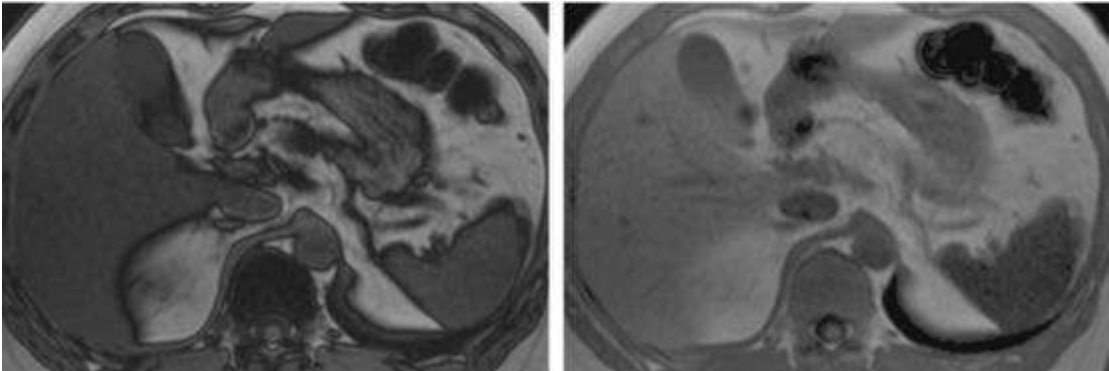

*T1WI同反相位成像:這是MR診斷脂肪肝的“金標(biāo)準(zhǔn)”。在T1WI同相位圖像上,脂肪肝的信號(hào)強(qiáng)度與正常肝組織相似;而在反相位圖像上,脂肪肝的信號(hào)強(qiáng)度會(huì)明顯降低。

(圖片說(shuō)明:左圖為T1WI同相位圖像,右圖為T1WI反相位圖像,可見(jiàn)脂肪肝在反相位圖像上信號(hào)強(qiáng)度明顯降低)